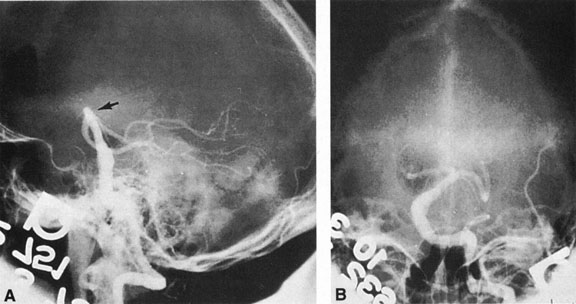

Most such aneurysms expand upward and forward, becoming located primarily anteriorly (Fig. 4). The optic nerves rise upward form the optic canal and may be inclined at a 45-degree angle such that the chiasm is more superiorly, as well as posteriorly, placed. It may be expected that uniocular ipsilateral visual loss would occur and progress before the contralateral field is involved because of chiasmal compression and before opposite nerve damage ensues. Although rapid visual loss has been reported, a longer duration (even years) is the rule. Rarely, the aneurysm may be more posteriorly placed or the chiasm more anteriorly fixed, resulting in initial involvement of the optic tract.20

Fig. 4. Giant suprasellar (supraclinoidal) aneurysms. A: Carotid arteriogram (lateral view) shows a huge aneurysm of the internal carotid artery in a 59-year-old woman with progressing visual loss. Coronal (B) and axial (C) magnetic resonance imaging sections of a similar case. Note partial thrombus formation (TR, 2100 ms; TE, 80 ms).